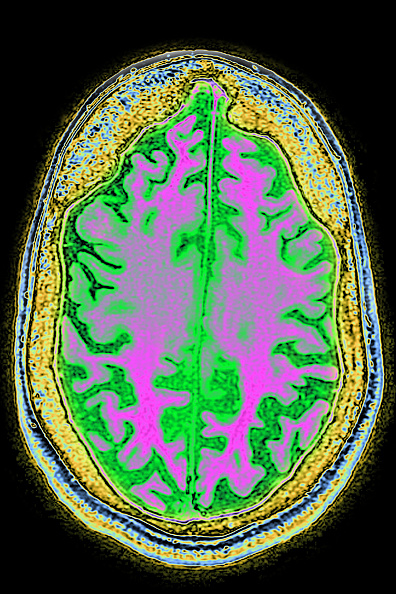

Dr Mac Shine, Robinson Fellow at the Brain & Mind Center at the University of Sydney, joins Luke Grant to talk about a new study published yesterday in the NEURON – about how researchers are working to map the brain to see what parts of the brain are involved when we concentrate – and what happens when we do complex tasks.

In this instance they used a brain imaging technique on participants who completed a Sudoku like puzzle finding that there were different patterns of brain activity – the trickier the task, the more the patterns changed.